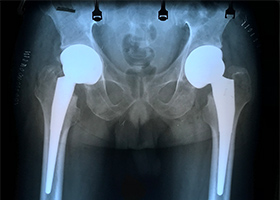

2 Year Follow Up Bilateral Hip Cambodia 2 Year Follow Up Bilateral Hip Cambodia 2 Year Follow Up Cambodia Bilateral Hip 2 Year Follow Up Cambodia Bilateral Hip 2 Year Follow Up Cambodia Bilateral Hip 2 Year Follow Up Cambodia Bilateral Hip